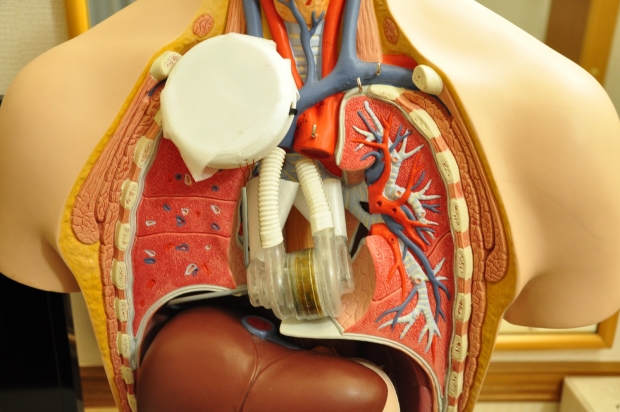

Un grup de studenți de la Universitatea de Medicină și Farmacie „Grigore T. Popa” din Iași a atras atenția comunității internaționale printr-o realizare revoluționară. Aceștia au creat cea mai mică inimă artificială din lume, un dispozitiv care poate fi implantat chiar și nou-născuților. Prototipul, prezentat în cadrul unei competiții mondiale desfășurate în Japonia, a impresionat atât juriul, cât și participanții.

Prototipul, dezvoltat de echipa MAVIS Artificial Heart, are dimensiuni extrem de mici și utilizează tehnologii avansate, precum imprimarea 3D. Dispozitivul este controlat printr-o aplicație mobilă, oferind medicilor și pacienților posibilitatea de a monitoriza funcționarea acestuia în timp real.

Studentul Robert Gatman a explicat că inima artificială are un design inovator, bazat pe un motor electromagnetic care levitează direct în sânge. Acest motor, cu formă cilindrică, acționează două pompe care înlocuiesc ventriculele pacientului. Energia necesară funcționării este furnizată wireless, eliminând riscul de infecții asociate cablurilor transcutanate.

„Un nou născut are nevoie undeva la doi litri de sânge pe minut. În centrul dispozitivului avem un motor care levitează electromagnetic chiar în sânge. El are forma cilindrică. La capătul cilindrilor avem două pompe, pompa dreaptă şi pompa stângă, care e formează acest dispozitiv care e însăşi inima. Dispozitivul este montat în locul ventriculelor pacientului, iar ulterior acest motor este pus în mişcare de către o componentă subcutanată.

Adică sub pielea pacientului. Această componentă va pune în mişcare motorul şi care va primi energie dinafară. Noi am optat să nu folosim cabluri care trec prin pielea pacientului, deoarece sunt cauzele a foarte mulţi factori de infecţii. Am decis să facem transfer de energie wireless, precum ai încărca un telefon wireless. Pacientul, cât şi medicul, pot monitoriza cum funcţionează inima cu ajutorul unei aplicaţii care se poate instala şi pe telefon, dar poate fi şi pe calculator”, a explicat Robert Gatman, student în anul IV la Facultatea de Bioinginerie.

Prezentarea dispozitivului a fost unul dintre momentele marcante ale competiției. Echipa românească a surprins audiența scoțând dintr-un manechin un prototip de inimă pentru adulți, urmat de dezvăluirea celei pentru nou-născuți. Acest element-surpriză a captat imediat atenția și a generat reacții entuziaste din partea juriului și a celorlalți competitori.